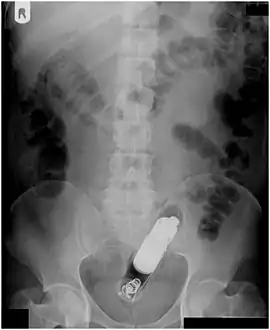

Abdominal X-ray showing small packages of cocaine swallowed by a trafficker.